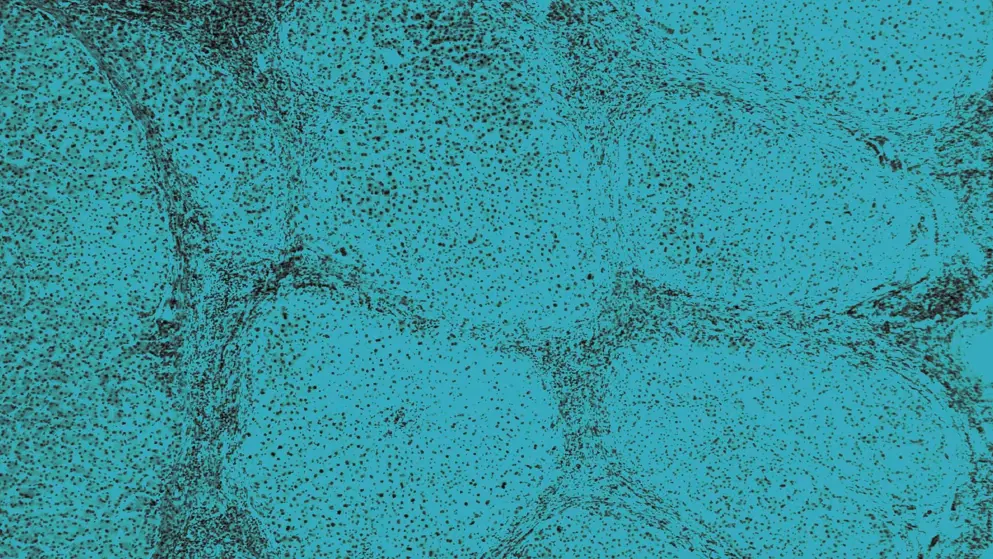

Hepatocellular accumulation of misfolded AAT Z protein polymers is an established risk factor for the development of cirrhosis in people homozygous for the Z allele4,6,7. Homozygosity for the Z allele (PiZZ) is therefore considered the highest risk factor for severe and early-onset disease and is present in 95% of cases8,9.